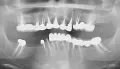

Нужна консультация по ортопедии (весь рот кариеса, мосты, коронки, пломб). Что нужно панорамный снимок или личное присутствие?

• В идеале требуется трехмерный снимок КЛКТ и, безусловно, личное присутствие пациента.